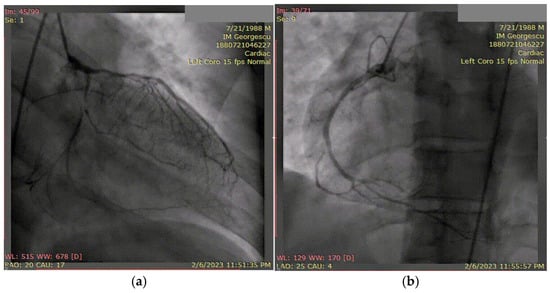

3.1. Case 1

3.2. Case 2